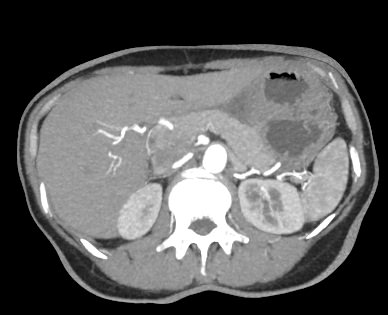

В компьютерном томографе излучатель рентгеновских лучей установлен в кольцевой части аппарата и, непрерывно вращаясь вокруг зоны исследования, производит послойное сканирование в различных плоскостях. В результате получаются снимки анатомической зоны в мельчайших подробностях, а после цифровой обработки полученных данных – точные трехмерные объемные модели исследуемой области. При этом изображения органов можно приблизить, повернуть в разные стороны, что значительно повышает точность диагностики различных заболеваний.

Для улучшения визуализации мягкотканных структур (внутренних органов, клетчаточных пространств, связок, мышц, сухожилий, кровеносных сосудов и лимфатических узлов) в ряде случаев проводится дополнительно контрастное усиление. Для этого пациенту внутривенно вводится йодсодержащий контрастный препарат, который активно поглощает рентгеновские лучи. Благодаря способности контраста накапливаться в патологических участках, они становятся хорошо видны на снимках КТ. Контрастное усиление позволяет оценить состояние сосудистой системы, выявить участки воспаления и опухолевые образования. С помощью контрастирования удается выявлять опухоли минимальных размеров, определить точные размеры и границы опухоли, степень ее воздействия на окружающие ткани.